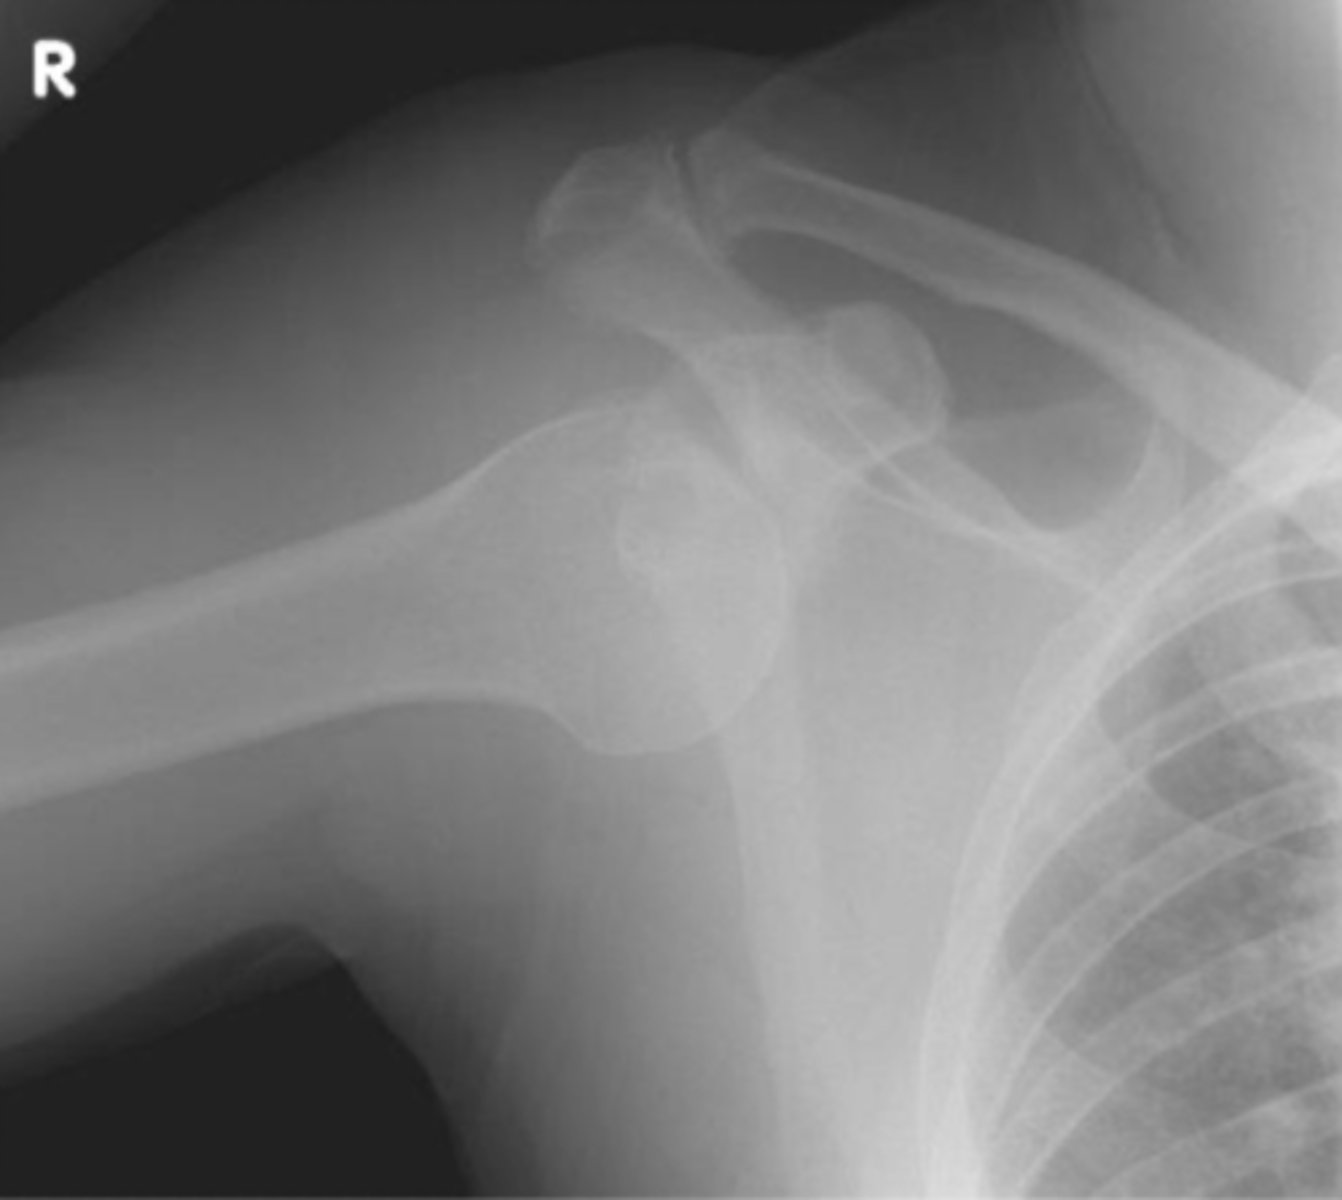

Anterior/Inferior displacement of the GHJ

What is the issue?

Posterior dislocation of GHJ